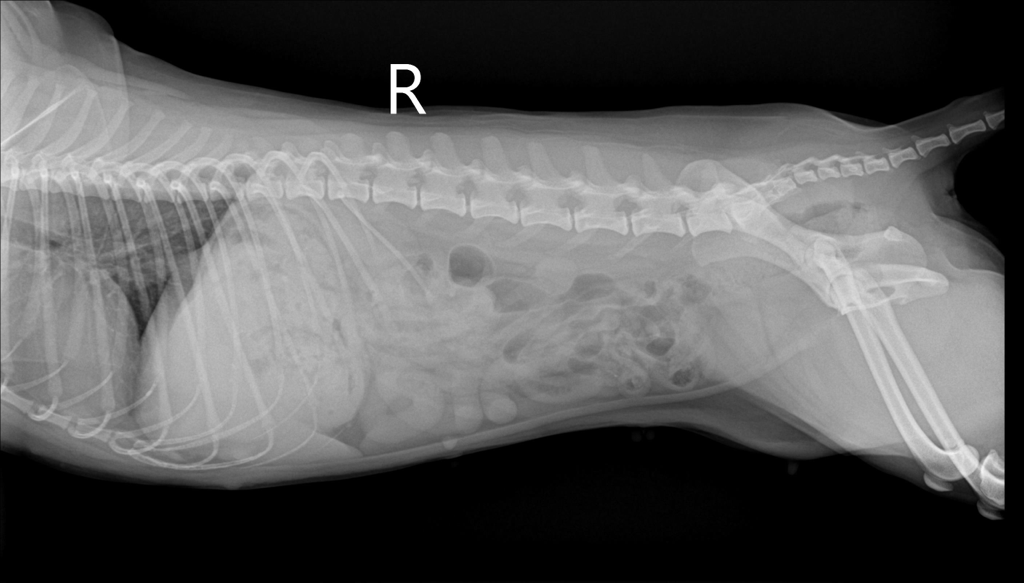

우리 강아지 디스크 일까요..?움직이지 않아요

평소랑 달리 움직이없고 헥헥 거리며 끙끙 앓아요 사진상으로 디스크 의심갈만한 문제가 없어보인다는데 전문가들의 의견이 궁금합니다 ㅜ ㅜ

방사선 만으로는 디스크를 확진할 수 없습니다.

그외 신경검사인 심부통증 반응과 자세반응 등 신경계 검사와 확진을 위해서는 CT촬영과 MRI 촬영이 필요합니다.

화살표를 해둔 부분의 디스크 공간이 좁아 보이는 양상이 경미하게 관찰되어 의심해볼만한 가능성은 있으나 디스크는 엑스레이 사진으로 진단되는 질환이 아니기에 다른 검사 결과에서 디스크를 강력히 의심할만하다면 MRI 검사가 추천됩니다.

반복된 촬영에서 재현성도 확보되어 증상이 지속된다면 이 사진을 근거로 MRI 촬영을 해봐야 하는 사항으로 판단됩니다.